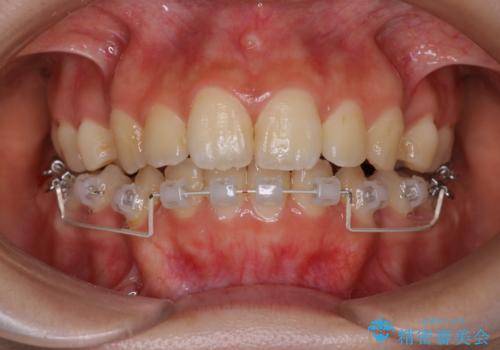

- 矯正装置

- ハーフリンガル

- 治療期間

- 3年

- 口元が出ていることを主訴に来院されました。

歯を抜いてスペースを作ることで、前歯を下げることができました。

ハーフリンガルということで治療期間が3年近くかかりましたが、口元もしっかり下がり満足していただきました。